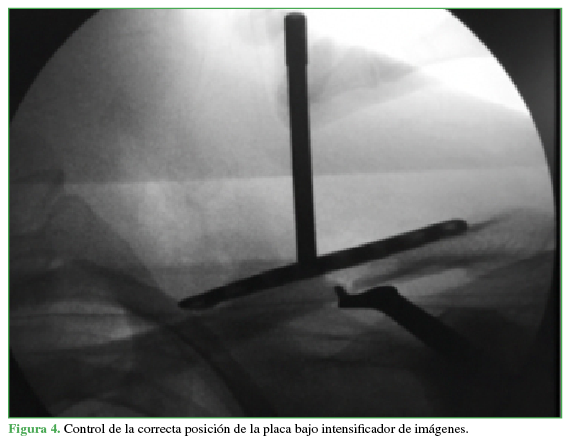

Bajo anestesia general, el paciente es colocado en posición de silla de playa sobre una mesa radiolúcida. Se infiltra lidocaína al 1% con epinefrina en la zona quirúrgica, antes de la incisión longitudinal de aproximadamente 3 cm a lo largo del borde superior de la clavícula a nivel del foco fracturario (Figura 1). Se profundizan planos y se alcanza el plano óseo identificando el trazo de fractura. Si se identifica una rama del nervio supraescapular, se la protege. Se liberan los fragmentos principales y se efectúa una reducción directa con la ayuda de daviers y se fija con un tornillo interfragmentario, de ser necesario. Si existiera un tercer fragmento, se procede a la simplificación de la fractura con un tornillo cortical para posteriormente lograr la reducción definitiva. Luego, la disección se extiende a nivel submuscular en la cara superior de la clavícula, sobre ambos fragmentos principales (Figura 2) para deslizar una placa regional anatómica bloqueada de 3,5 mm hacia medial y lateral del foco fracturario (Figura 3). Se controla la correcta posición de la placa bajo intensificador de imágenes, mediante las proyecciones anteroposterior y craneocaudal15 (Figura 4).

Control de la correcta posición de la placa bajo intensificador de imágenes.

PropiaA continuación, la placa se fija con un tornillo cortical medial y otro lateral, para mantener la reducción y apoyar la placa al hueso. Estos tornillos se pueden colocar por el mismo abordaje o en forma percutánea (Figura 5A). Posteriormente se coloca, en forma percutánea, el resto de los tornillos bloqueados, mediales y laterales, con ayuda de la torre de bloqueo (Figura 5B).